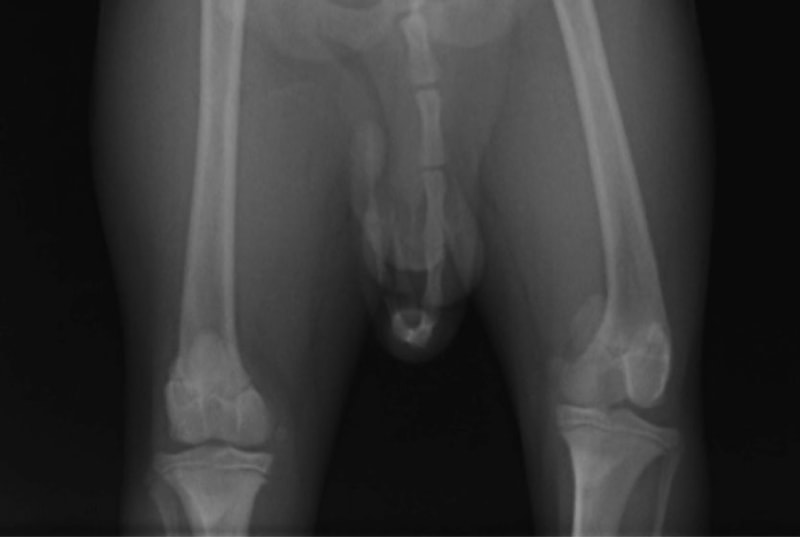

■ 症例20 ポメラニアン 8ヶ月 1.8kg

左右膝蓋骨脱臼 グレードⅢ

2ヶ月前から間欠的跛行が認められ、両膝の膝蓋骨脱臼整復術を行った。

手技は縫工筋及び内側広筋の解放、脛骨粗面の外側転位、滑車ブロック形造溝術、内外側関節包の縫縮を選択し実施した。

右側の膝蓋骨脱臼は上記手技で整復されたものの、左側はそれのみでは膝蓋骨が浮く様子が認められた。その為、PDS縫合糸にて膝蓋靱帯を1糸のみ縫合し、靱帯の縫縮を行った。

膝蓋骨脱臼は膝関節における膝蓋骨の内外側の脱臼と定義されるが、時として単純な内外の脱臼ではなく、膝蓋骨が大きく前方に浮き上がるように脱臼する場合がある。特にトイプードルやポメラニアンといった犬種に多く認められる。

内側脱臼に加えて前方への浮き上がりを矯正する為に、従来より脛骨粗面転移により膝蓋靭帯を外方と下方に引っ張り、固定する方法を選択する。膝蓋骨の前方への浮き上がりが軽度の場合は、従来法ではなく関節包の縫縮で対応していた。しかし、一部の症例で膝蓋骨の動きが悪くなり伸展機構が円滑に機能せずロボット様歩行になるケースがあった。

その為、膝蓋靭帯自体を縫縮する方法を採用した。この方法により、膝関節の伸展機構を妨げず膝蓋骨の軽度の浮きを矯正することが可能となった。

本症例の経過は良好である